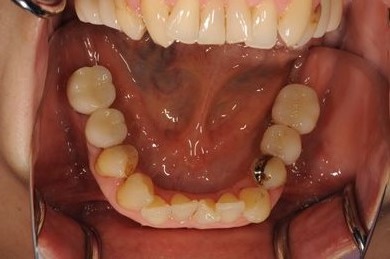

骨再生スピードインプラント治療+セラミック治療

| 主訴 | 左上の歯に以前から歯周病があり、多少のぐらつきがあったが、ここにきていよいよ限界になりました。食事に影響があるので、インプラントを視野に、とりあえずは抜歯をと思っています。 | ||||||||||||||||||||||||||||||||

| 治療方針 | サイナスリフトにて上顎洞を拳上し、インプラント治療を可能にする。抜歯と同時にインプラント埋入を行い、治療期間を短縮する。 | ||||||||||||||||||||||||||||||||

| 治療内容 | インプラント9本(抜歯即日スピードインプラント、サイナスリフト)、ハイブリッドセラミッククラウン12本(ハイブリッドセラミック用土台3本) | ||||||||||||||||||||||||||||||||

| 総治療費 | 4,157,213円 | ||||||||||||||||||||||||||||||||

| 治療期間 | 1年0ヶ月 |